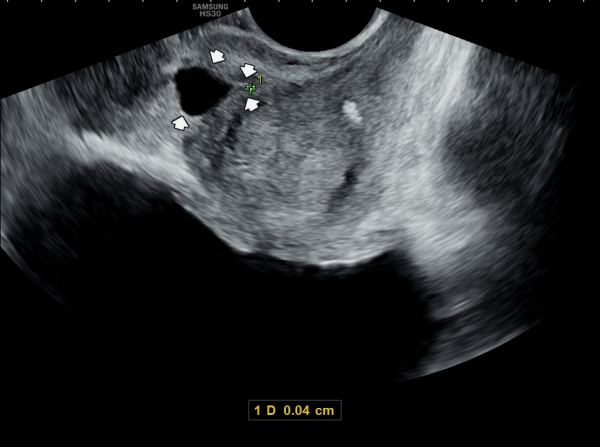

사정관의 입구가 좁아져 사정관의 낭종이 진행되는 초음파 사진입니다.

This ultrasound image shows narrowing of the opening of the ejaculatory duct, which is causing the progression of an ejaculatory duct cyst.

The narrowing interferes with normal fluid flow, allowing the cyst to gradually enlarge over time.

사정관의 입구가 좁아져 정낭과 정관등의 순환 장애로 정관을 통해 사정관으로 사출될 정자들이 사정되지 못하로 정낭으로 역류하여 다발성 정낭과 혈정액과 정낭의 결석등을 일으키는 초음파 사진입니다.

This ultrasound image shows narrowing at the opening of the ejaculatory duct, which causes circulatory flow problems in the seminal vesicles and vas deferens.

Because of this blockage, sperm that should normally be ejaculated through the ejaculatory duct cannot pass properly. Instead, they flow backward into the seminal vesicles, leading to multiple seminal vesicle cysts and sometimes blood in the semen (hematospermia) and intermittantly caculi formation.